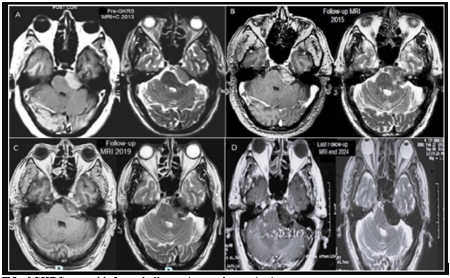

Figure 1: Serial MRI of GKRS treated left cerebellopontine angle meningioma;

A- pre-GKRS MRI in 2013 reveals a wide dural-based left cerebellopontine angle meningioma exhibits homogeneous contrast enhancement in T1 weighted image and isointense to gray matter in T2-weighted images. The lesion extends anteriorly to the tip of the Petro clival region, projecting obstructively through the pours of the left internal acoustic canal. The lesion slightly indented the brainstem. Tumor volume is 7.446 cm³, with maximum diameters of 19.8 x 31.8 x 30.1 mm (XYZ), treated with GKRS with 12Gy peripheral prescription dose to the 35% isodose line.

B- Follow-up MRI T1 and T2 with contrast images in 2015 shows the GKRS treated left CPA meningioma in 2023 exhibits a stationary growth pattern, characterized by signs of heterogeneous degeneration and reduces contrast enhancement.

C- Follow-up MRI T1&T2+ contrast images in 2019 reveals a mild increase in the z-coordinate axis that was noted before in the 2017. Current MRI, demonstrates hypointense signal across all pulse sequences, characterized by heterogeneous faint enhancement and increasing areas of necrosis. The treated left CPA meningioma continued to compress the ipsilateral cistern accompany by mild perilesional edema on the anterior superior surface of the left cerebellar hemisphere.

D- The most recent follow-up MRI in September 2024 shows no significant changes in the size or extent of the treated left CPA meningioma in 2013 compared to earlier scans. Notably, the lesion is now wholly calcified. It exhibits very low signal intensity on T2-weighted images and mixed iso- and low signal on T1 images. There have been no changes in the previously noted mild perilesional edema or the mass effect.